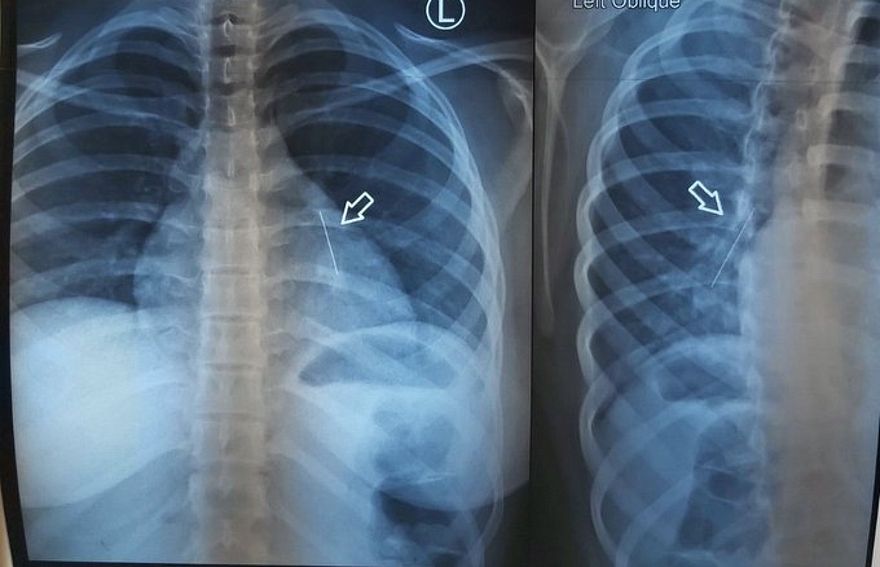

މިދިޔަ އަހަރުގެ ޖުލައި މަހުގެ ތެރޭގައި، ކާއެތިކޮޅު ތާށިވެގެން، އުމުރުން ފަސް އަހަރުން ދަށުގެ ކުއްޖާ އެންމެ ފުރަތަމަ ގެންދިޔައީ އައިޖީއެމްއެޗަށެވެ. ރޯގާ ޖެހި ނޭވާލާން އުނދަގޫވާތީ، އެންމެ ފުރަތަމަ ހެދީ އެ ކުއްޖާގެ ސީޓީ ސްކޭނެކެވެ. ނޭވާލާ މައި ހޮޅިއަށް ވުރެ ވެސް އެތެރޭގައި ކާއޭތިކޮޅު ތާށިވެފައިވާކަން އެނގުނީ އެ ސްކޭނުންނެވެ.

ނޭވާލާހޮޅީގައި ތާށިވެފައިވާ ކާއެތިކޮޅު ނެގުމަށް އައިޖީއެމްއެޗުގެ ޑޮކްޓަރުން ވަރަށް މަސައްކަތް ކުރި އެވެ. ގަނޑުކޮށްގެން ވެސް އެ އެތިކޮޅު ނުނެގުނު އިރު، އެކަމުގެ ތެރޭގައި ކުއްޖާގެ ހާލު ސީރިއަސްވެ، ވެންޓިލޭޓަރުގައި ވެސް ބާއްވަން ޖެހުނެވެ.

އެންމެ ބޮޑު މައްސަލައަކަށް ދިމާވީ، ކާއެތިކޮޅަށް ގިނަ ދުވަސްވެ މަސް އަރާފައި އިނުމެވެ. އެހެންވެ، ޑޮކްޓަރުން ނިންމީ ކުއްޖާ ރާއްޖޭން ބޭރަށް ފޮނުވާލާށެވެ.

އައިޖީއެމްއެޗުގައި ކުޑަކުއްޖާ ބެލި އެތެރެހަށީގެ ޑޮކްޓަރު މުހައްމަދު އަލީ މިއަދު ވިދާޅުވީ އިންޑިއާގައި ދެ ފަހަރެއްގެ މަތިން ބްރޮންކޮސްކޮޕީ ނުވަތަ ފުއްޕާމޭގެެތެރެއަށް ހޮޅިއެއް ވައްދައިގެން، ކާއެތިކޮޅު ނަގައިފައިވާ ކަމަށެވެ.

"ކާއެތިކޮޅު އިނީ ވަރަށް އެތެރޭގައި. އަޅުގަނޑުމެން ފުރަތަމަ މަސައްކަތް ކުރީ ވެސް، ބްރޮންކޮސްކޮޕީ ހަދައިގެން ކެމެރާ ލައްވައިގެން އެ އެތިކޮޅު ނެގޭތޯ. އެކަމަކު އެތިކޮޅު ތާށިވެފައި އޮތް ހިސާބަށް ދެވޭވަރުގެ އެހާ ކުޑަ ސައިޒުގެ [ބްރޮންކޮސްކޮޕީ]އެއް އަޅުގަނޑުމެން އަތަކު ނެތް،" ޑޮކްޓަރު ވިދާޅުވި އެވެ.